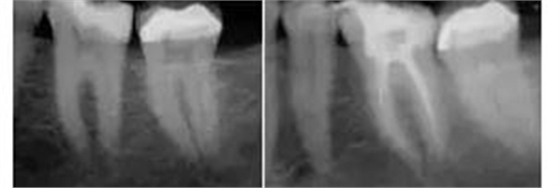

工作尖僅被置于開髓洞形的冠方。當(dāng)沖洗液占據(jù)整個根管系統(tǒng),開啟設(shè)備后震蕩波向所有方向傳導(dǎo),高效地清除有機組織殘留物。通過這種激光激活湍流現(xiàn)象,臨床醫(yī)師遵照PIPS使用方法,無需將工作尖放入每個根管,從而避免為了將標(biāo)準(zhǔn)針頭送入細小脆弱的根尖結(jié)構(gòu)(通常是根尖1/3)進行沖洗而擴大、去除更多的牙體組織。其結(jié)果是根管便利形態(tài)的獲得變得更保守、微創(chuàng)和仿生(圖3)。

圖3:左,術(shù)前。 右,經(jīng)PIPS處理后充填的術(shù)后片。牙齒預(yù)備至#25/06錐度。注意保守的便利形保持了更多的根管系統(tǒng)初始形態(tài)、減少了大號根管銼的使用、保存了更多的牙本質(zhì)結(jié)構(gòu)。